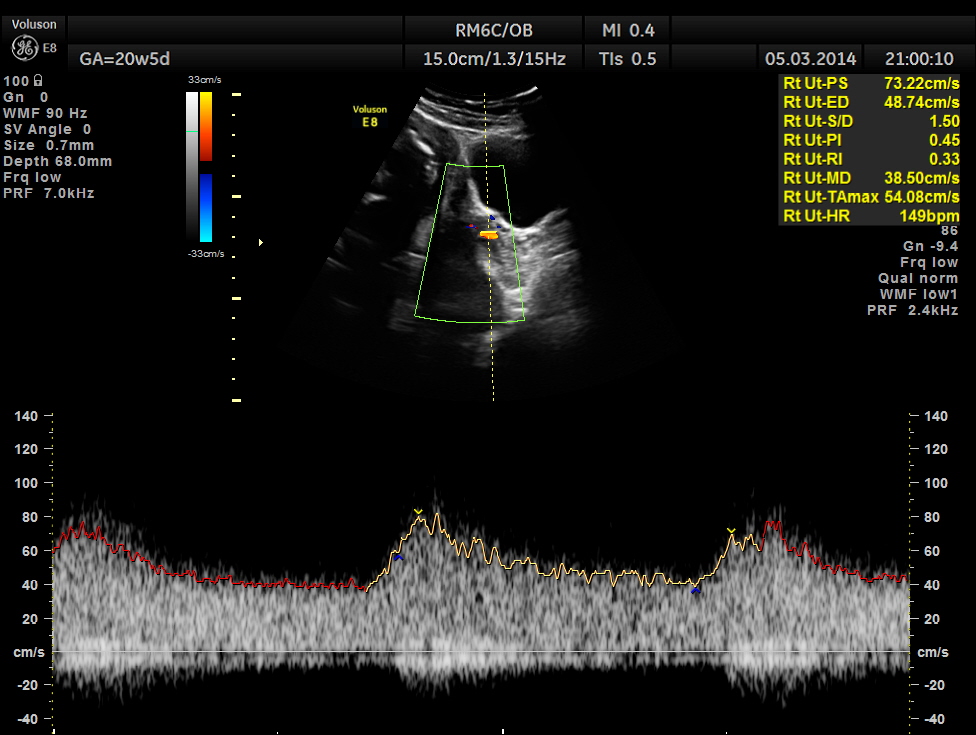

Spectral Doppler pictures are given below.

Umbilical arterial arterial P.I. and R.I. are high for the GA. and the cerebro placental ratio appears to be borderline > 1.0 and < 1.1 for the R.I.